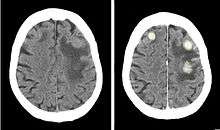

CT scan of a patient with brain metastases from breast cancer, before (left) and after (right) injection of iodinated contrast.

Iodinated contrast is a form of intravenous radiocontrast (radiographic dye) containing iodine, which enhances the visibility of vascular structures and organs during radiographic procedures. Some pathologies, such as cancer, have particularly improved visibility with iodinated contrast.